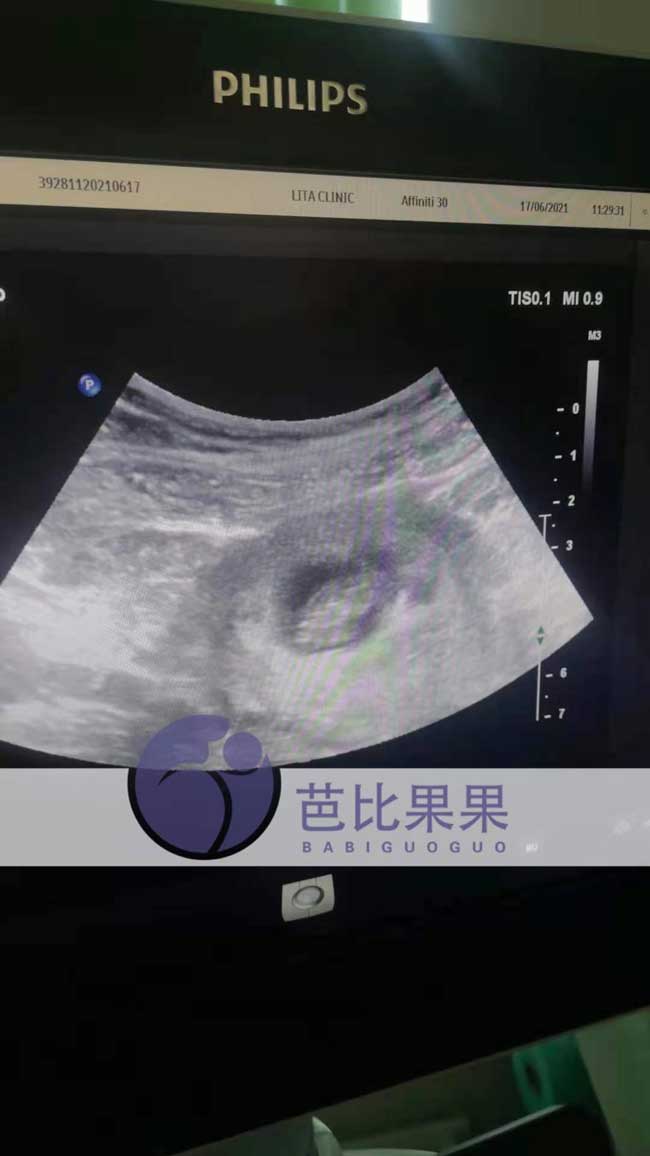

L女士乌克兰试管按照相关管理按时做好第二次B超

马丽塔产检有一套标准的管理,L女士乌克兰试管做了第二次B超,腹内宝宝比上次大了不少,发育良好。